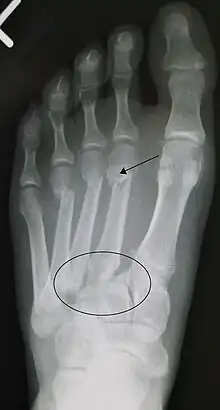

![]() | |

| An X-ray of a Lisfranc injury | |

In a high energy injury to the midfoot, such as a fall from a height or a motor vehicle accident, the diagnosis of a Lisfranc injury should, in theory at least, pose less of a challenge. There will be deformity of the midfoot and X-ray abnormalities should be obvious. Further, the nature of the injury will create heightened clinical suspicion and there may even be disruption of the overlying skin and compromise of the blood supply. Typical X-ray findings would include a gap between the base of the first and second toes.[8] The diagnosis becomes more challenging in the case of low energy incidents, such as might occur with a twisting injury on the racquetball court, or when an American Football lineman is forced back upon a foot that is already in a fully plantar flexed position. Then, there may only be complaint of inability to bear weight and some mild swelling of the forefoot or midfoot. Bruising of the arch has been described as diagnostic in these circumstances but may well be absent.[9] Typically, conventional radiography of the foot is utilized with standard non-weight bearing views, supplemented by weight bearing views which may demonstrate widening of the interval between the first and second toes, if the initial views fail to show abnormality. Unfortunately, radiographs in such circumstances have a sensitivity of 50% when non-weight bearing and 85% when weight bearing, meaning that they will appear normal in 15% of cases where a Lisfranc injury actually exists.[10] In the case of apparently normal x-rays, if clinical suspicion remains, advanced imaging such as magnetic resonance imaging (MRI) or computed tomography (CT scan) is a logical next step.[11]